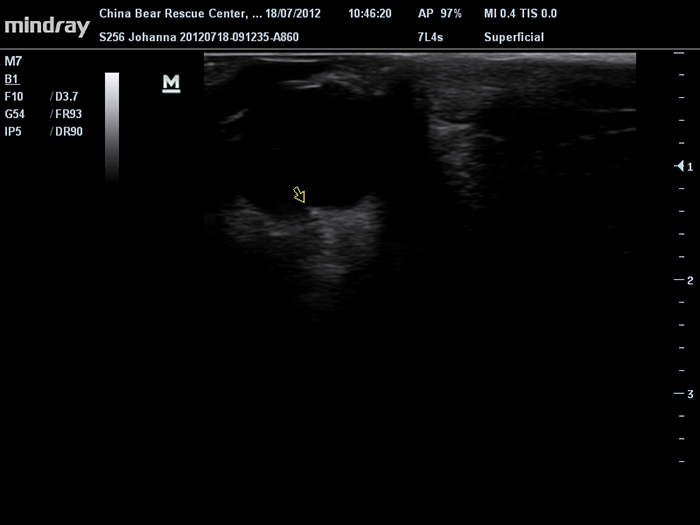

Mindray M7 Vet – Digimed